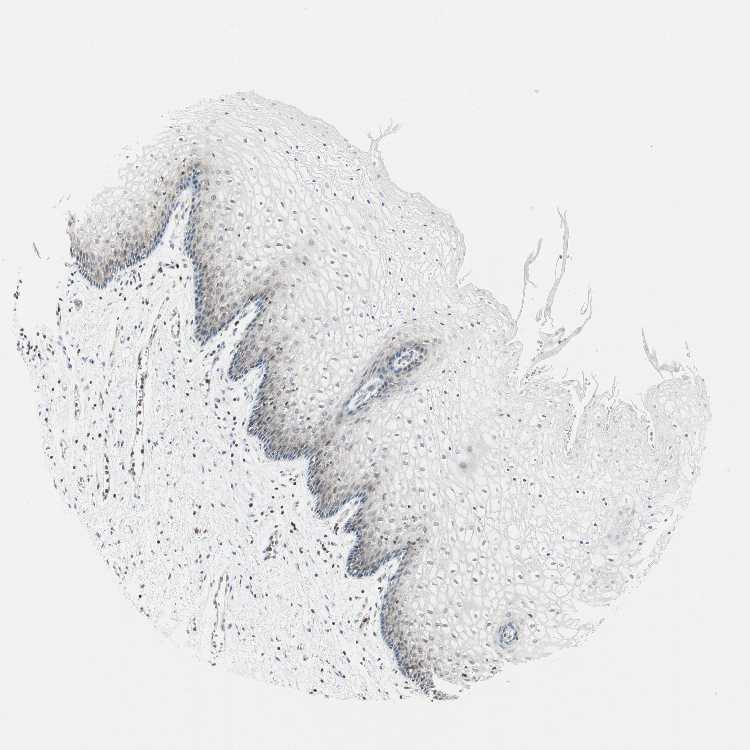

VAGINA - Antibody stainingi

Antibody staining in the annotated cell types in the current human tissue is reported as not detected, low, medium, or high, based on conventional immunohistochemistry profiling in selected tissues. This score is based on the combination of the staining intensity and fraction of stained cells.

Each image is clickable and will lead to virtual microscopy that enables deeper exploration of all samples and also displays staining intensity scores, fraction scores and subcellular localization as well as patient and tissue information for each sample.

Antibody HPA046833Antibody CAB004545

Squamous epithelial cells Not detectedLow